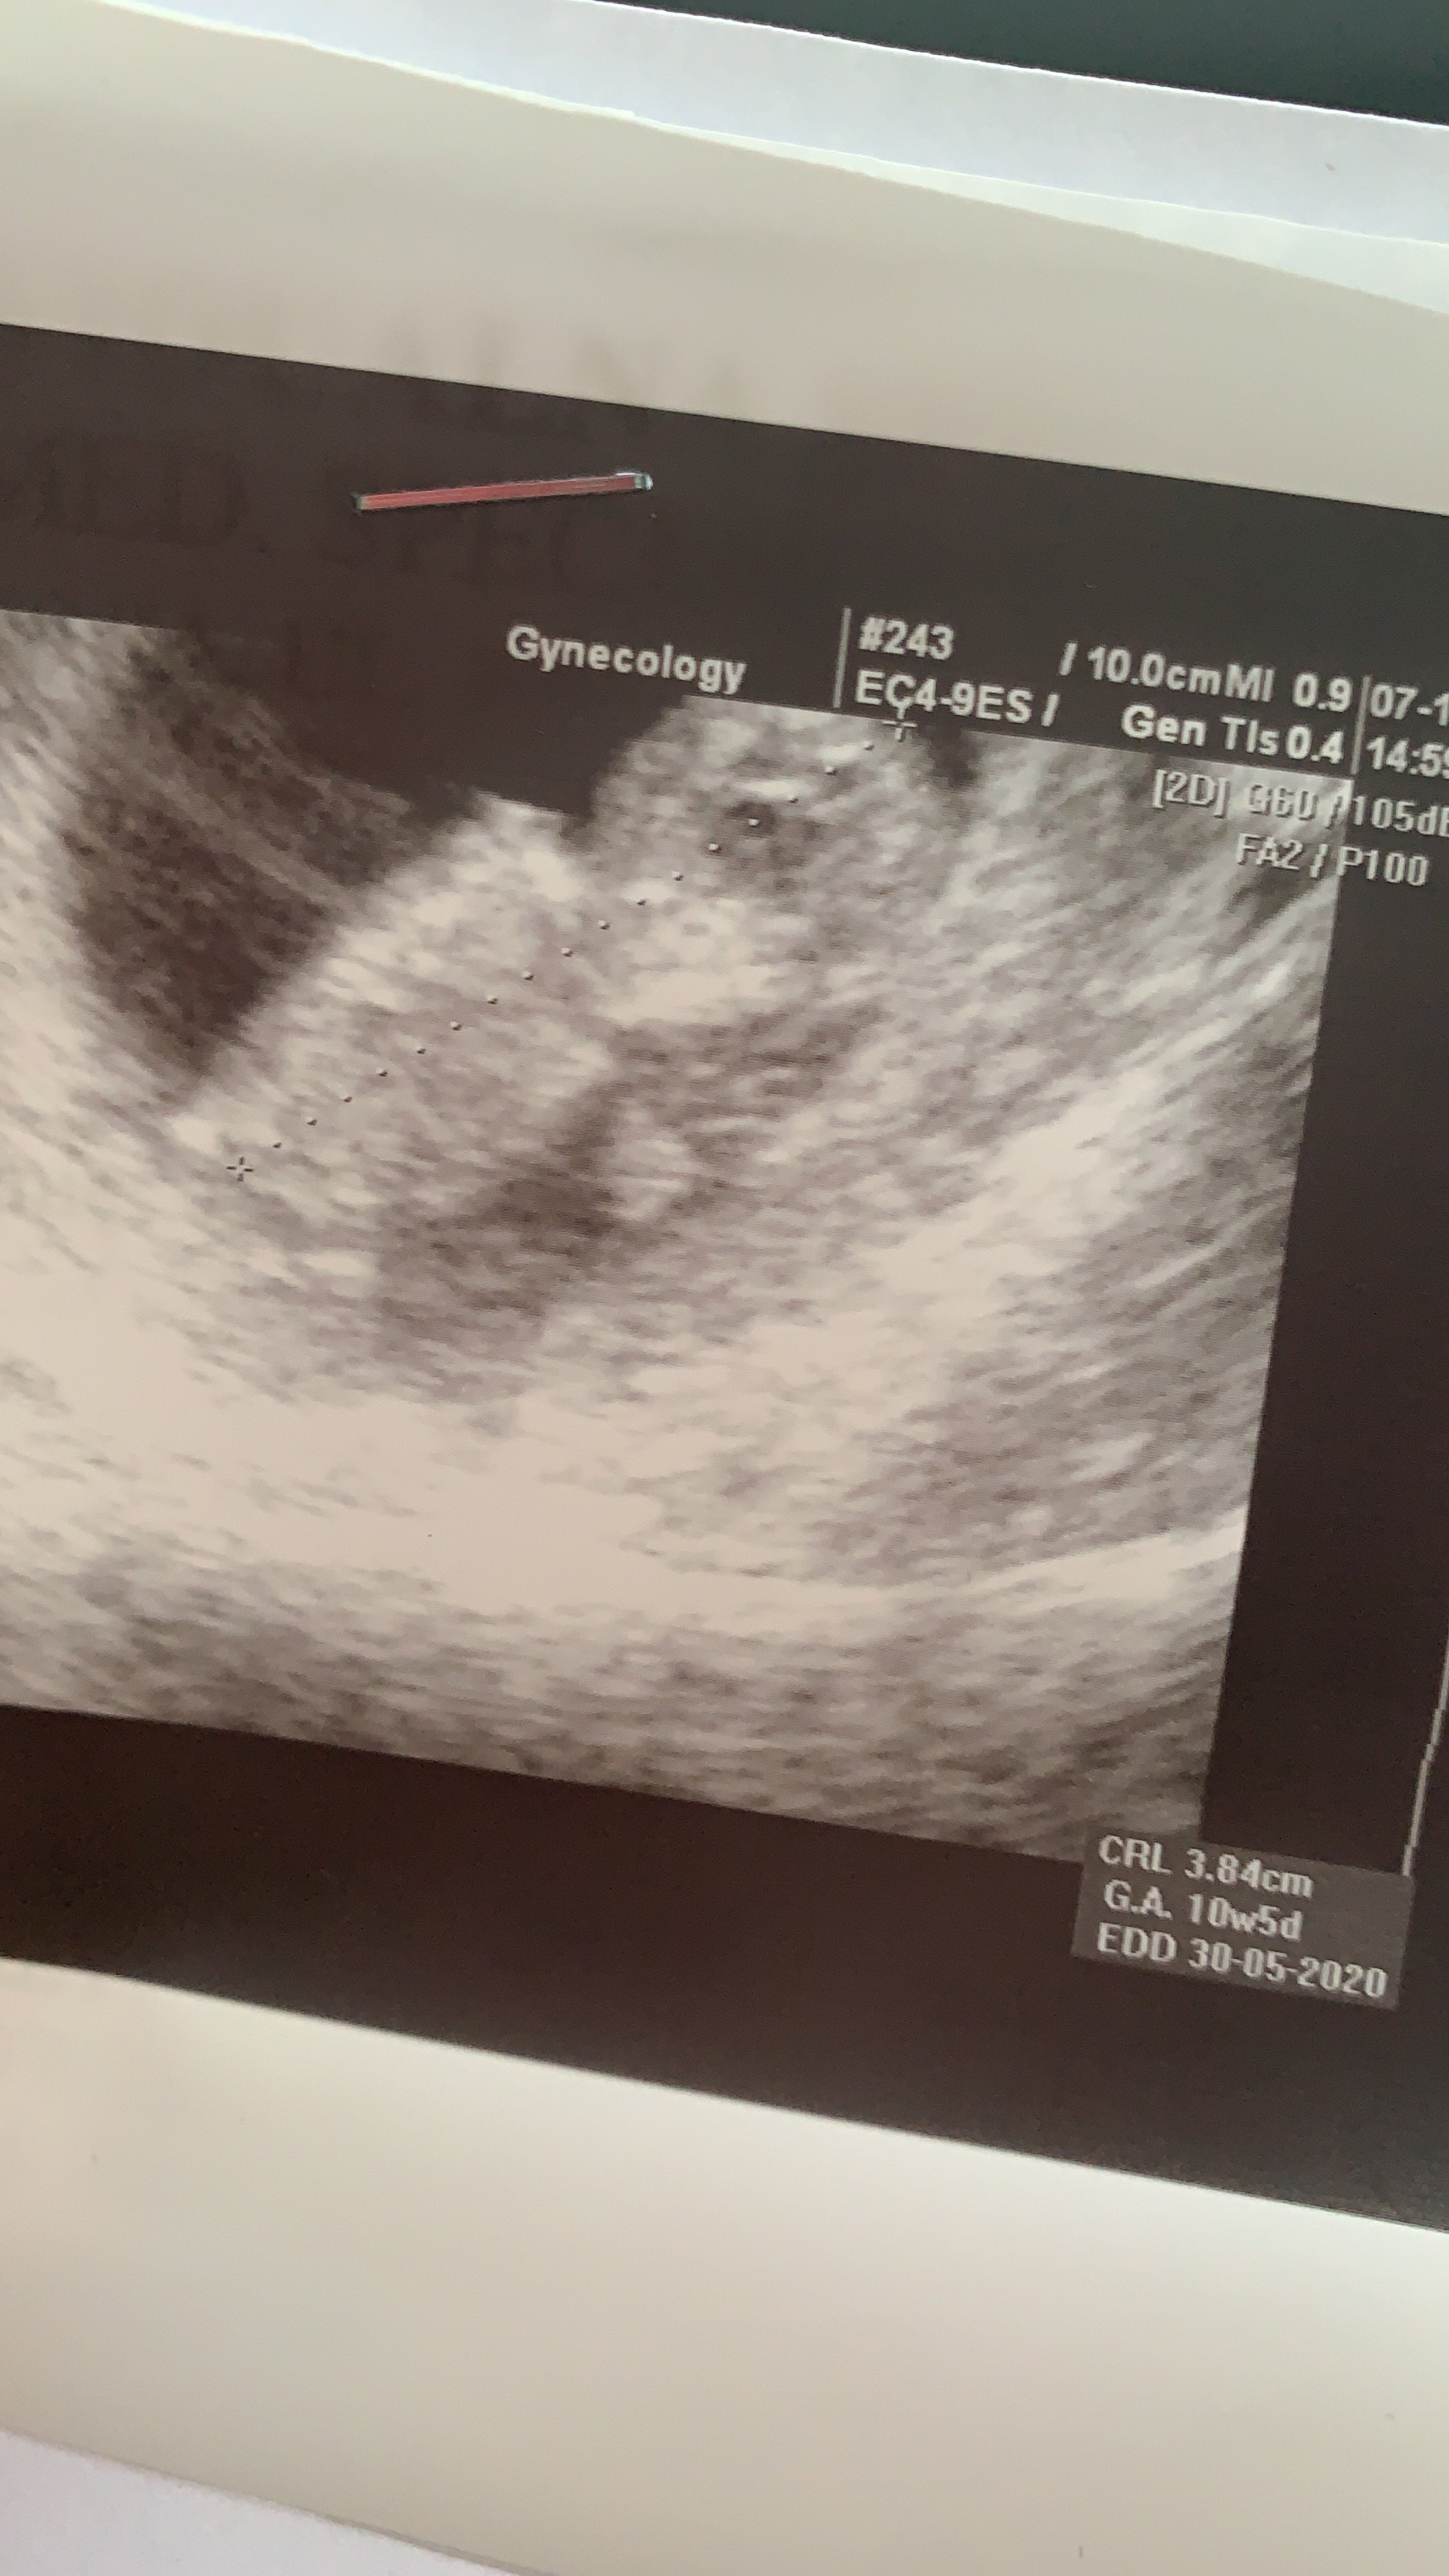

I jestem po :) Dzidzia super tylko, że za mała na prenatalne jednak. Wstępnie sprawdził i prz.karkowa wygląda okey. Wychodzi 10+5 i data na 30.05.2020 wg. USG. Z ciekawostek powiedział mi, że to bzdura, że po poronieniu wczesnym (do 11tc) ciąża jest z komplikacjami, i że on ma kilka pacjentek, które tylko i wyłącznie po poronieniu zaszły od razu w ciąże i urodziły zdrowe, donoszone dzieci :D Lubię tego doktorka - od razu jestem spokojniejsza. Zobacz załącznik 1042509